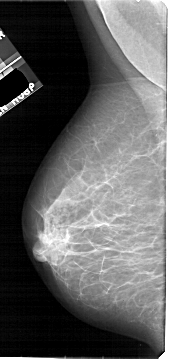

A_1922_1.LEFT_MLO

LEFT_MLO LINES 5371 PIXELS_PER_LINE 2536 BITS_PER_PIXEL 12 RESOLUTION 43.5 NON_OVERLAY